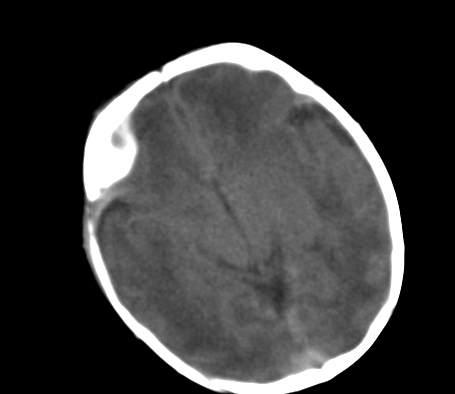

标题: PED0831:患儿,5天,是HIE吗?

患儿,出生时正常,第5天突然呕吐两次,无发热及抽搐。

片示:双侧大脑半球脑实质密度降低,皮髓分界尚清,左侧顶部脑沟内见铸形高密度影,脑中线结构居中。

2、hie并少量蛛网膜下腔出血。